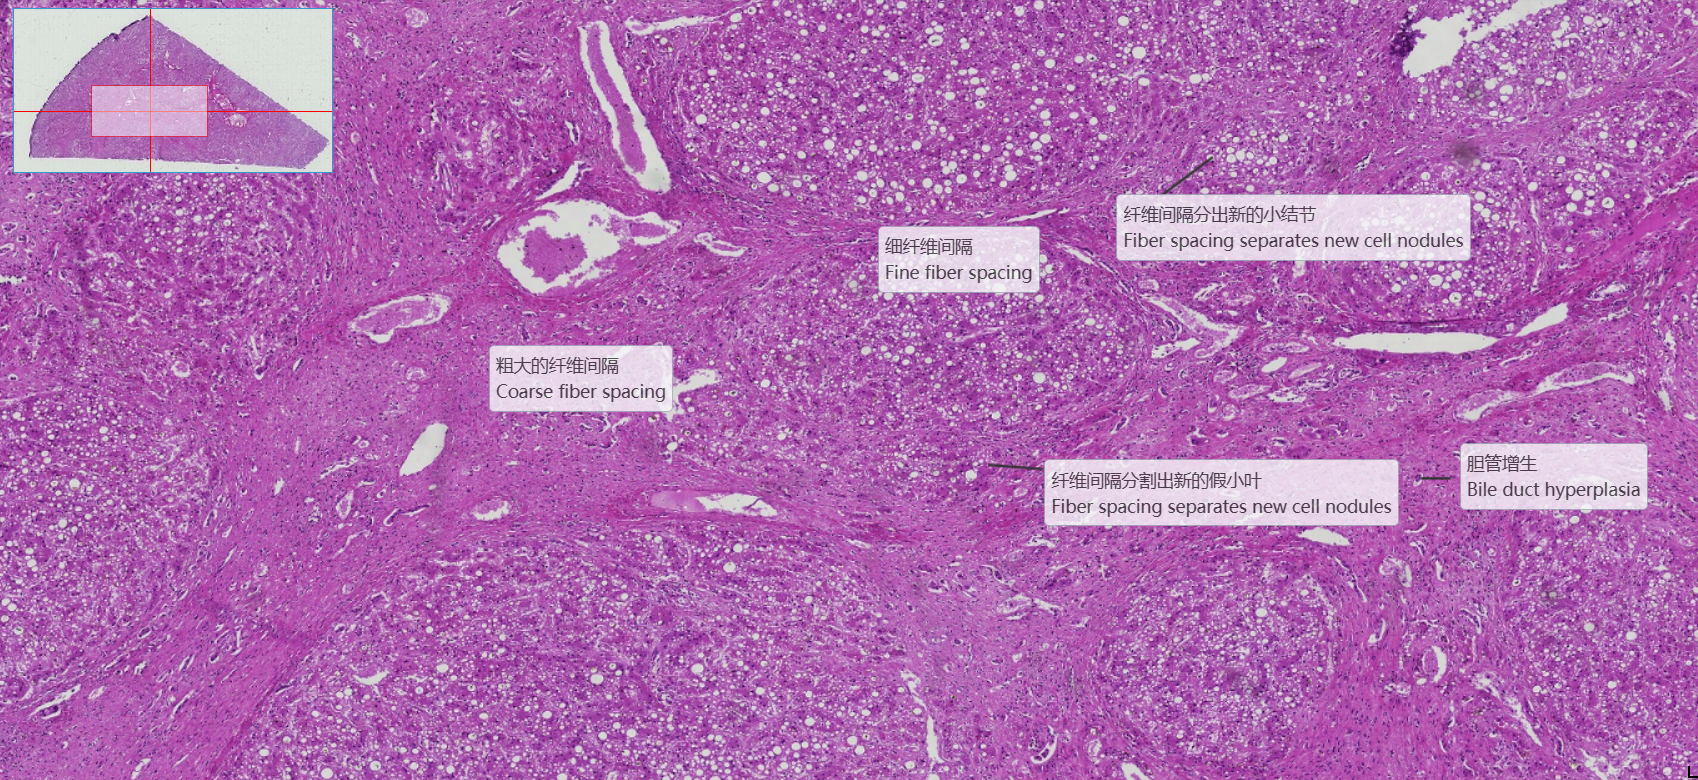

2 坏死后性肝硬化

低倍镜观察:1. 肝小叶:呈多边形或不规则形,界限不清。中央静脉位于肝小叶内,但并非完全位于中央,且有的肝小叶中找不到中央静脉(与肝小叶的切面有关)。肝板及肝血窦均比较清楚。2. 门管区:在邻近几个肝小叶之间的结缔组织内,三种伴行的管道:(1)小叶间动脉:腔小壁厚,可见中膜环行平滑肌。(2)小叶间静脉:腔大壁薄,有时可见与血窦相连续。(3)小叶间胆管:管径较小,管壁衬以单层立方上皮,细胞呈立方形,胞浆清明,细胞核呈圆形,着色较深。